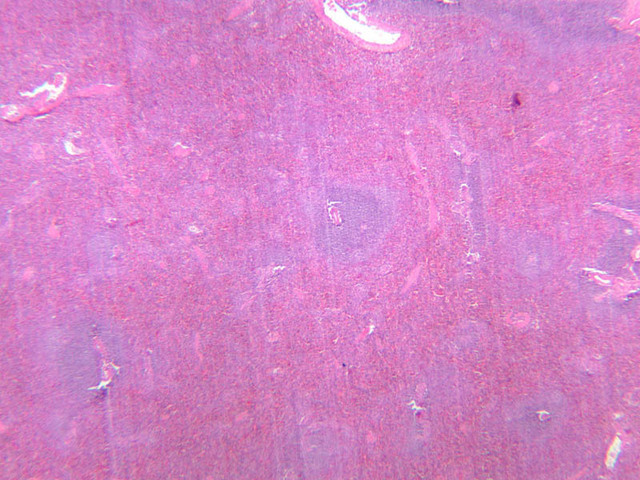

In lymphatic nodules and nodes the term primary nodule refers to a nodule of homogeneously, tightly packed small lymphocytes. When lymphatic nodules have germinal centers they are called secondary nodules. A germinal center contains lighter staining, "B" lymphocyte precursors. Mitotic figures should be easily spotted in the core of the nodule. Compare these cells with the mass of small more differentiated lymphocytes that surround the germinal center. Some of these lymphocytes are cytokine producing T-Helper cells that are stimulating the proliferation of the lymphoblasts.

Lymph Nodes

When foreign substances or antigens get into body tissues, such materials are usually taken into the lymph and transported to aggregations of lymphoid tissue called lymph nodes (slide A-32, H&E [2.5x-labeled, 10x, 20x, 40x] [2.5x-labeled, 10x, 20x] [2.5x, 10x, 20x-labeled, 40x]; A-33, H&E [2.5x, 10x, 20x, 40x]; A-34, retic [2.5x, 10x, 20x, 40x-labeled]; A-35, H&E [2.5x, 10x, 20x, 40x]), which are composed of lymph nodules invested by a distinct connective tissue capsule. The node is visibly separable into a cortex, where the densely stained nodules are concentrated, and a light staining medulla (A-32 [2.5x, 10x-labeled, 20x, 40x]). Strands, or trabeculae, of connective tissue separate the node into cortical compartments and join centrally in the node to emerge at the indented side known as the hilus. Small arteries and veins enter and leave the node at the hilus, being distributed in the node through the trabeculae. Capillary branches from the arteries are spread throughout the lymphoid node. Multiple afferent lymphatic vessels penetrate the capsule of the node, emptying into a subcapsular sinus which is a relatively cell-free zone (A-32 [2.5x, 10x, 20x, 40x-labeled]). Unidirectional flow of lymph from the afferent lymphatics into the sinus is assured by the valves in the vessels. From the subcapsular sinuses, lymph percolates through the relatively unobstructed cortical sinuses to the medulla. During this flow the lymph is filtered by phagocytes and foreign antigens are presented to lymphocytes by dendritic cells, the resident antigenpresenting cells. Nodules are formed as needed and subsequently disappear. Lymph finally reaches the medullary sinuses bounded by wide cords of tissue and passes out of the node at the hilus through the sole efferent lymphatic vessel.

The lymphoid tissue of a node is thus divisible into the nodules in the cortex and looser cords in the medulla. In the cortex, carefully examine a secondary nodule, composed of a dense outer rim of cells and a more loosely organized core (germinal center). In between the nodules find larger cells with pale, oval nuclei. These are reticular cells and will be most easily identified in the reticular-stained preparation (A-34 [2.5x, 10x, 20x, 40x] [10x, 20x, 40x]). The reticular fibers cells make up the CT scaffolding of the lymph node. Note that there are fewer reticular fibers in the germinal centers. Medium-sized cells with pale nuclei, particularly cells with a prominent nucleolus, may be progenitor cells of new lymphocytes. Macrophages present in the nodule are hard to distinguish unless they contain phagocytosed material. In the medulla, cell types in the cords are easier to distinguish because cytoplasmic size and extent can be seen. For example, the differences between large lymphocytes and reticular cells can be seen. Several types of granular leukocytes are frequently found in the cords in addition to the expected population of lymphocytes and plasma cells.